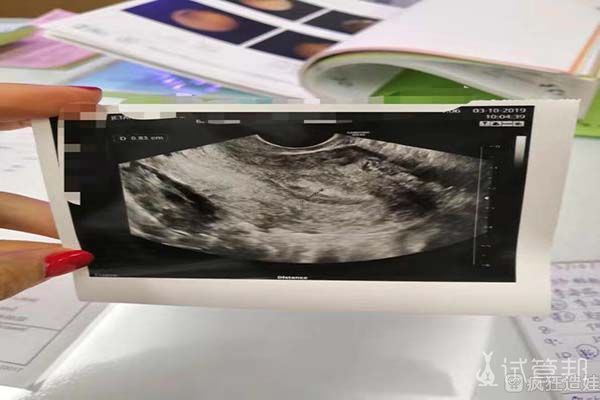

接下来就是胚胎移植了。我说过我的子宫是存在小问题的,所以第一个周期,我的子宫内膜情况没有达标,没有进行胚胎移植。我是在第二个周期的时候,进行的胚胎移植,胚胎移植了一个男胚。胚胎移植后第十天做的验孕,一次成功。